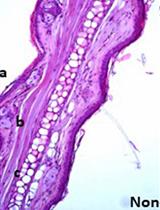

In vivo biofilms grown on medical devices are necessary to understand the interactions of the fungal biofilm and the host environment in which it is most commonly found. This protocol describes a way to grow Candida albicans biofilms on the interior lumen of central venous catheters surgically implanted into rats, which mimics quite well the clinical cases of biofilms found on human central venous catheters. These infected catheters can then be studied via a multitude of different experiments, including cell counting by plating, imaging the catheters under light or electron microscopy, or comparing the relative content of in vivo biofilms to in vitro biofilms and planktonic cultures. These biofilms also provide enough high quality RNA for transcriptional profiling.